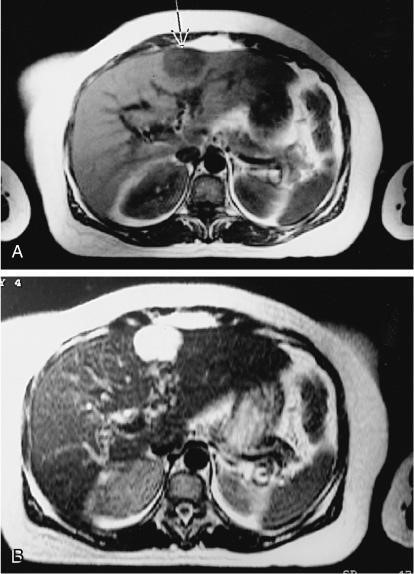

MRI of Hemangioma

• MRI: high-intensity area.